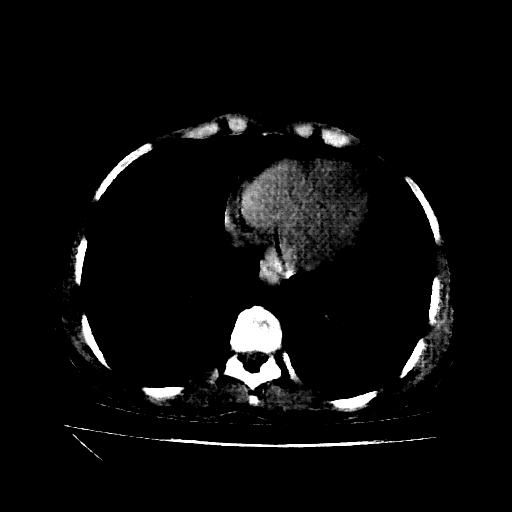

Reconstructed NATIVE CT scan (cycle consistency)

Full window (WL 1023.5, WW 4095 β†’ Low βˆ’1024, High +3071)

Actual HU range: [-1024.0, 702.5]

Lung window (WL -600, WW 1500 β†’ Low βˆ’1350, High +150)

Actual HU range: [-1189.6, 150.0]

Mediastinum window (WL 40, WW 400 β†’ Low βˆ’160, High +240)

Actual HU range: [-160.0, 240.0]